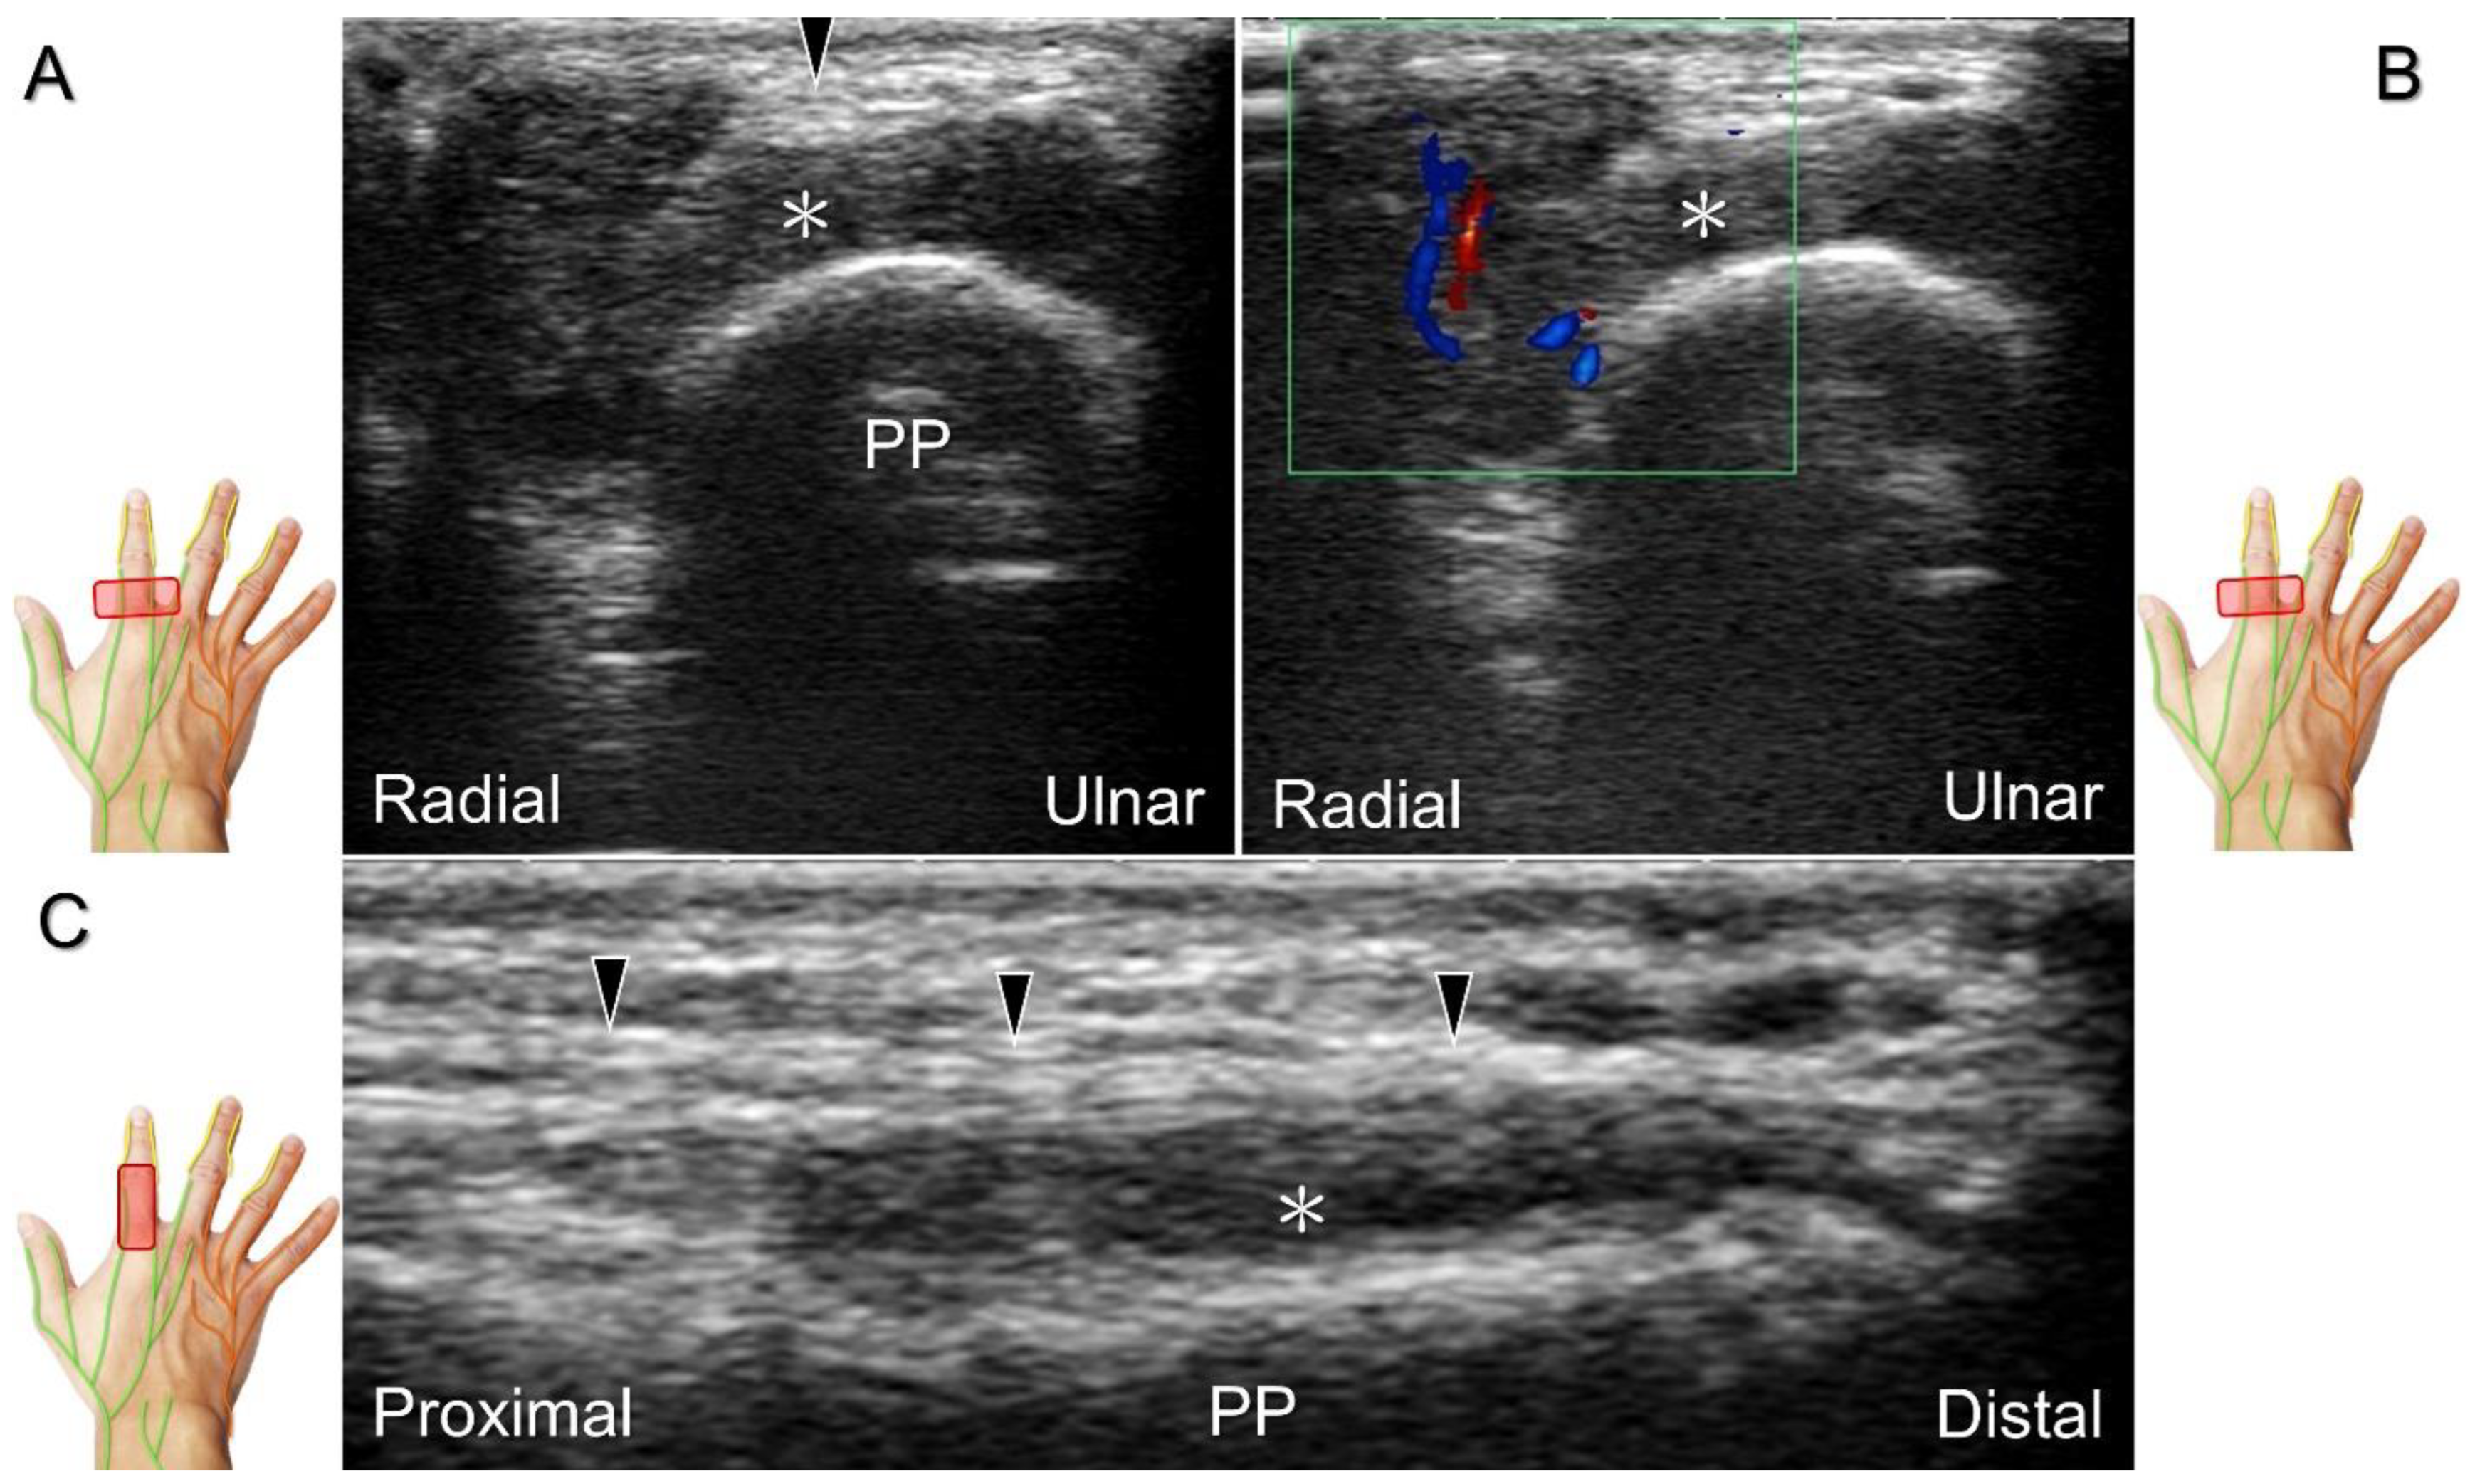

Scanning Technique

The transducer is positioned on the axial plane of the dorsal metacarpal joint in the target digit. The dorsal proper digital nerves can be found on either side of the sagittal band (Figure 33A). The transducer is moved proximally and the dorsal common digital nerves can be observed superficial to the extensor (usually the extensor digitorum proprius) tendons (Figure 33B). By returning to the level of the sagittal band and moving the transducer distally, the dorsal proper digital nerves can be seen superficial to and alongside the central slip of the finger extensor tendon (Figure 33C). Alternatively, moving the transducer distally toward the proximal phalanx of the first to the radial aspect of the fourth phalanx allows observation of the nerve fascicles of the palmar proper digital nerve originating from the median nerve (Figure 33D).

Clinical Implication

Injuries to the dorsal common digital nerve typically occur in the workplace as a result of cutting or crushing. However, the nerve can also sustain damage due to various other factors such as fracture, ganglia, tenosynovitis, tumor (Figure 34), foreign objects, or boxing, which may cause contusion over the first knuckles (Figure 35).

US imaging may reveal a neuroma in cases where patients report chronic allodynia and/or tingling sensation in the affected digit (Figure 36). To perform hydrodissection, the in-plane approach can be utilized in the nerve’s short axis after identifying the extensor digitorum tendons and the dorsal metacarpal arteries (Figure 37).

Figure 33. Sonographic imaging of the dorsal common digital nerve on the metacarpal bone (A), toward the metacarpal head (B). Dorsal proper digital nerves on the proximal phalanx (C), and the terminal nerve originating from the palmar proper digital nerve on the distal phalanx of third finger (D). Arrowheads: dorsal common digital nerve; arrows: palmar proper digital nerve. MCP: metacarpal bone; SB: sagittal band; E: extensor tendon; Cs: central slip; PP: proximal phalanx; T: terminal band; DP: distal phalanx; DIO, dorsal interosseous muscle.

Figure 34. In the short-axis view, the proper digital nerve is seen as irritated by a giant cell tumor (A) with increased vascular signals (B). The association between the proper digital nerve and the tumor is delineated in the long-axis view (C). Black arrowheads: proper digital nerve; PP: proximal phalanx; *: giant cell tumor.

Figure 35. Sonographic imaging reveals irritation of the ulnar aspect of the dorsal common digital nerve due to extensor tendon subluxation resulting from a tear in the sagittal band. Arrowheads: dorsal common digital nerve; asterisk: tear of the sagittal band. SB: sagittal band; E: extensor tendon; MCP: metacarpal bone.

Figure 36. Sonographic imaging (short-axis view) for a neuroma of the dorsal common digital nerve, proximal site (A) and the site of the lesion (B). Long-axis imaging of the nerve/neuroma (C). White arrowhead: normal dorsal common digital nerve; black arrowheads: neuroma. SB: sagittal band; E: extensor tendon; MCP: metacarpal bone; DIO: dorsal interosseous muscle; A: artery.